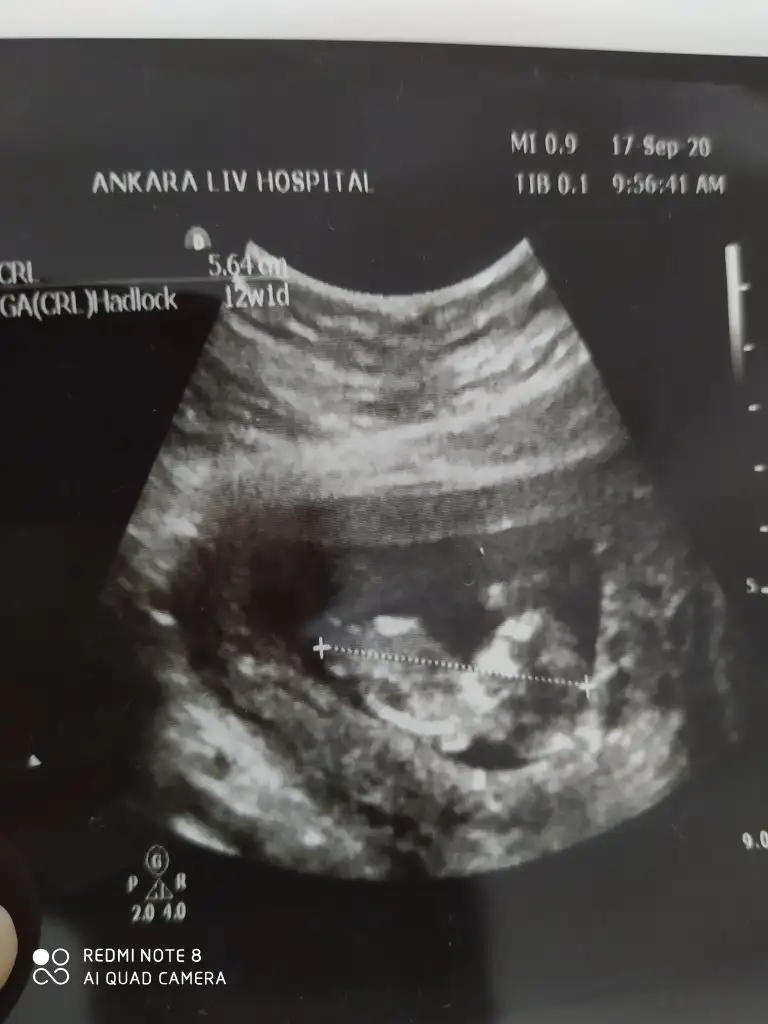

Daha küçükMerhabalar, bu ultrason fotografina gore cinsiyet tahmininiz var midirkalbi 6+4 de 150 atiyordu simdi 9+4 gozuktu bir hafta onden gidiyormus 180 atiyordu. Bir de sag tarafa yerlesmis

Olursa paylaşın 11 12 13 haftalar olur hiç net değil kız dedim ama olmayabilir net değil ilk bebekmi